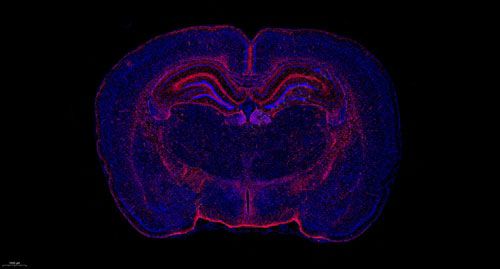

实验结果展示:

大鼠脑 普通切片扫描(荧光单标 双色)